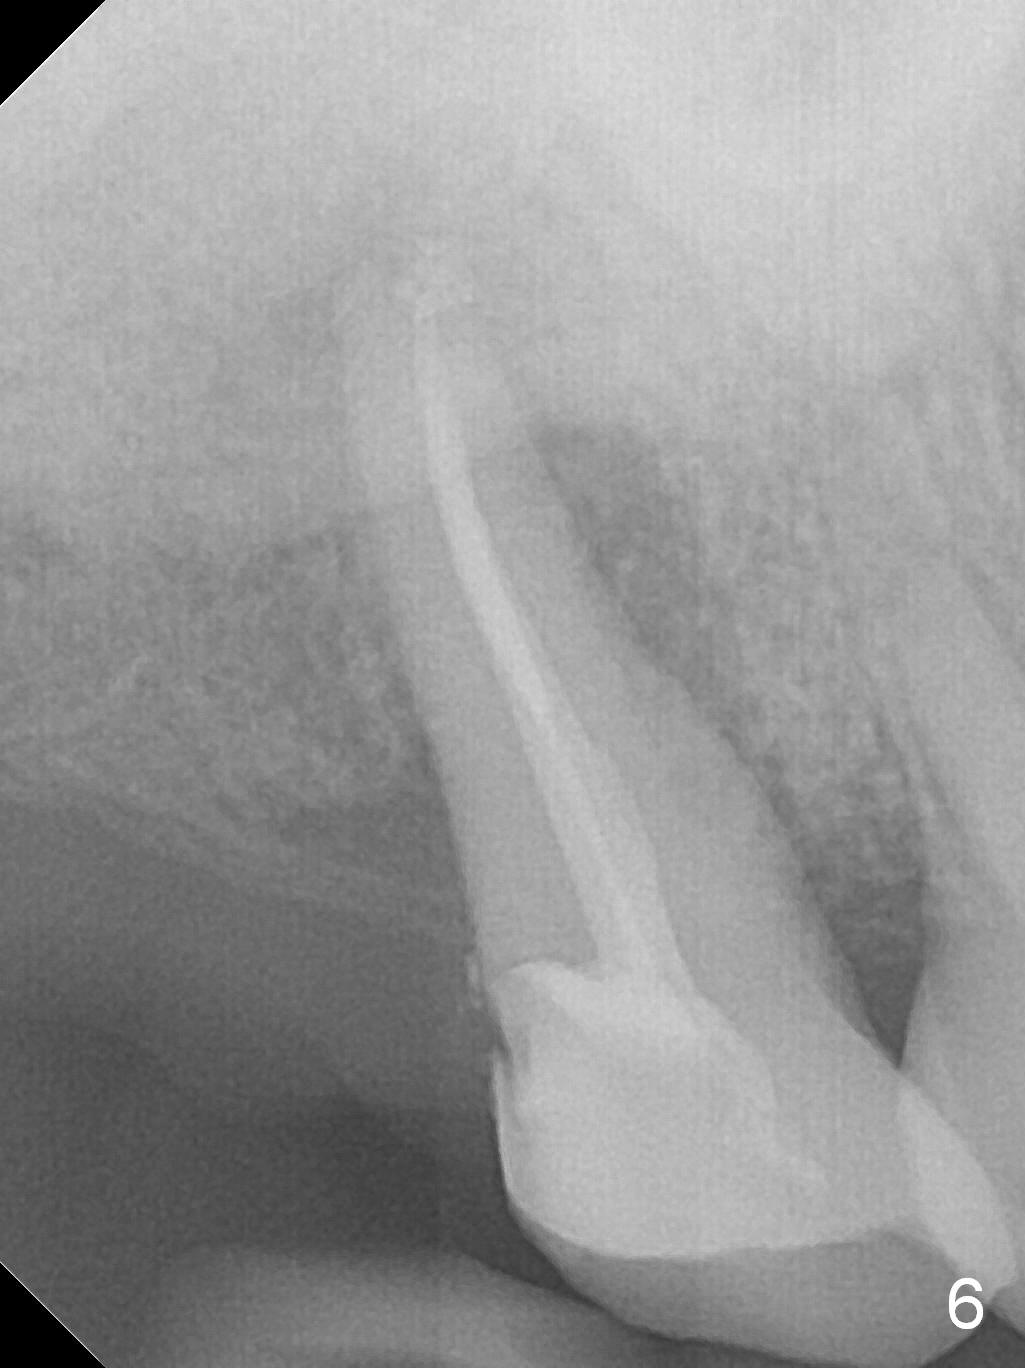

A 52-year-old woman presents to clinic with chief complaint "I can not bite in the upper right". Exam shows DO caries of the tooth #2 (Fig.1). After scaling & root planing and the tooth #1 extraction, pulpotomy is performed at #2. Two months later, pain recurs with swelling. When root canal therapy is finished at #2 (Fig.2-6), the tooth is found to have moderate mobility with guarded to poor prognosis. If the infection does not resolve, extraction and immediate implant seem to be necessary. Considering low bone density around the site of #2, a long implant is indicated (18 mm bone-level, Fig.7,8).